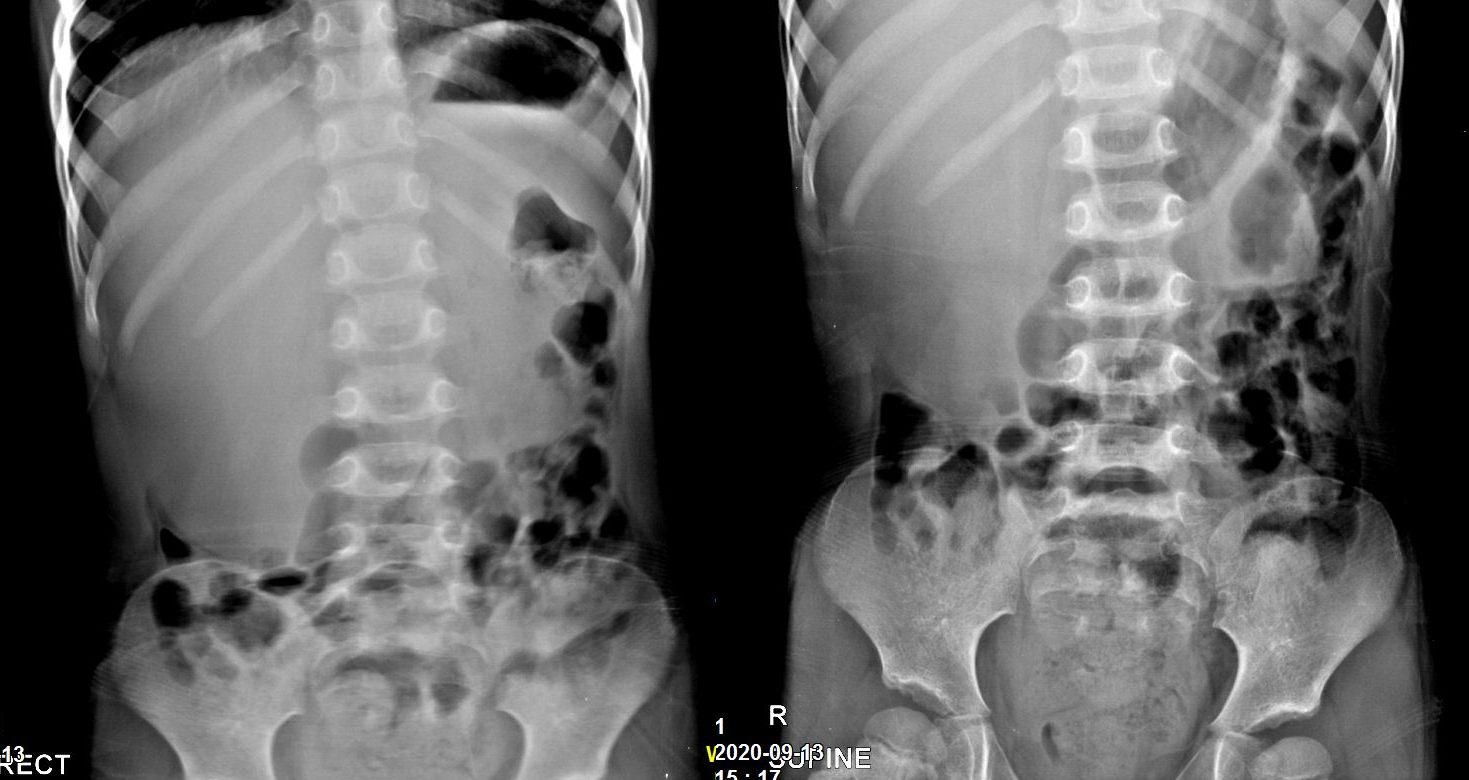

기본 혈액 검사에서 CBC, LFT, RFT, CRP 모두 참조범위 내의 수치를 보였고, 복부 단순영상촬영에서는 오른쪽 상복부에 미상의 음영 증가가 관찰되었다.

환아가 잠들었을 때 부드럽게 복부 촉진을 시도하니 덩어리가 만져졌는데 간비대 보다는 다른 것이 의심되었다. 초음파나 복부CT 같은 추가적인 영상검사가 필요하다고 판단하고 CT를 의뢰했으며 검사에서 수신증이 확인되었다.